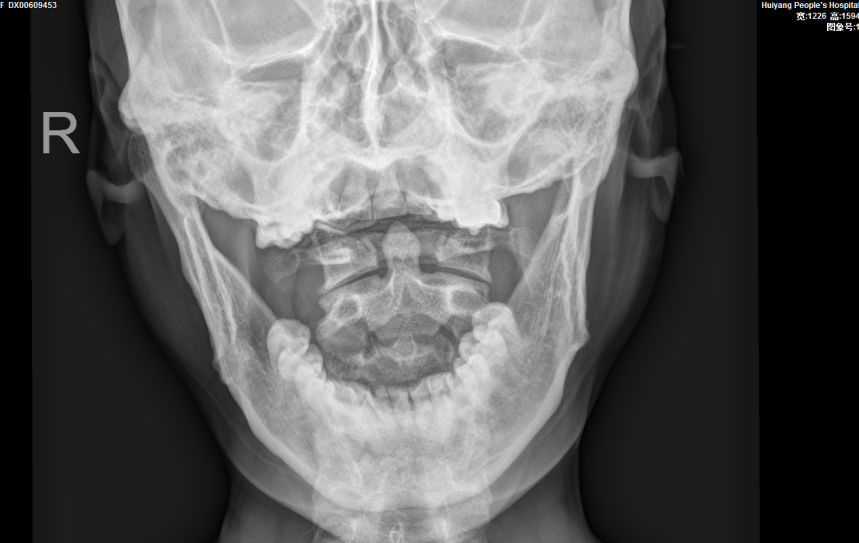

▲頸椎張口位示雙側寰樞關節不對(duì)稱

完善相關檢查後(hòu), 報告提示患者的頸椎生理曲度變直,序列如常。C2-7椎體邊緣可見不同程度骨質變尖、突起(qǐ)。C2/3椎間隙明顯變窄,呈前窄後(hòu)寬改變;餘椎間隙未見明顯變窄。項韌帶未見鈣化。寰樞關節開(kāi)口位見雙側不對(duì)稱,左側較右側爲寬(左側6mm,右側3mm),關節面(miàn)光整,寰椎、樞椎骨質未見明顯異常。周圍軟組織未見異常密度。